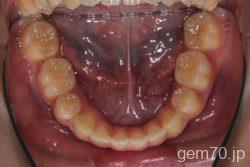

症状:開咬装置:セラミックブラケット | 抜歯世代:10代 | 高校生

主訴)前歯がかみ合わない

診断)開咬

年齢)18歳

使用装置)マルチブラケット装置

治療方法)抜歯 4|4/4|4

治療期間) 2年4ヵ月 通院回数 27回